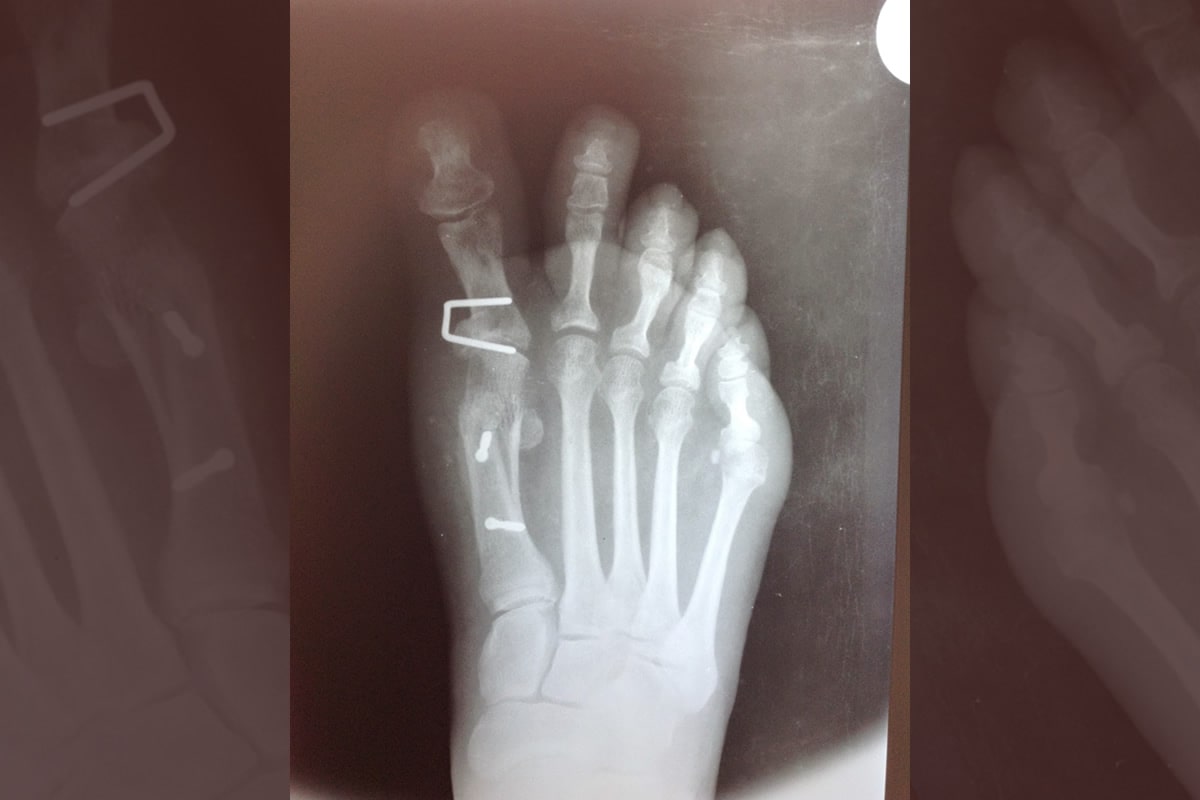

Como cirujanos del pie, consideramos muy importante una exploración clínica, radiodiagnóstica y ecográfica adaptada a cada patología y otras herramientas, como el estudio biomecánico de la marcha, nos permiten realizar un diagnóstico diferenciado, punto de partida clave para elegir la mejor vía de abordaje en cada caso y, en muchas ocasiones, crucial para la detección temprana de afecciones más complejas.

Cirugía Mínimamente Invasiva o Percutánea como Cirugía Abierta del Pie. Utilizando las técnicas más vanguardistas y menos lesivas en cada acto quirúrgico, adaptándolas a la patología de cada paciente.